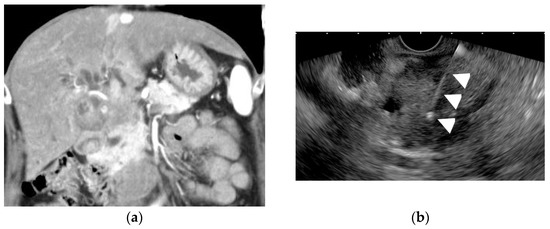

- Tanaka, K.; Katanuma, A.; Hayashi, T.; Kin, T.; Takahashi, K. Role of endoscopic ultrasound for gallbladder disease. J. Med. Ultrason. 2021, 48, 187–198. [Google Scholar] [CrossRef]

- Cho, J.H.; Park, J.Y.; Kim, Y.J.; Kim, H.M.; Kim, H.J.; Hong, S.P.; Park, S.W.; Chung, J.B.; Song, S.Y.; Bang, S. Hypoechoic foci on EUS are simple and strong predictive factors for neoplastic gallbladder polyps. Gastrointest. Endosc. 2009, 69, 1244–1250. [Google Scholar] [CrossRef]

- Lee, J.S.; Kim, J.H.; Kim, Y.J.; Ryu, J.K.; Kim, Y.T.; Lee, J.Y.; Han, J.K. Diagnostic accuracy of transabdominal high-resolution US for staging gallbladder cancer and differential diagnosis of neoplastic polyps compared with EUS. Eur. Radiol. 2017, 27. [Google Scholar] [CrossRef]

- Mizuguchi, M.; Kudo, S.; Fukahori, T.; Matsuo, Y.; Miyazaki, K.; Tokunaga, O.; Koyama, T.; Fujimoto, K. Endoscopic ultrasonography for demonstrating loss of multiple-layer pattern of the thickened gallbladder wall in the preoperative diagnosis of gallbladder cancer. Eur. Radiol. 1997, 7, 1323–1327. [Google Scholar] [CrossRef] [PubMed]

- Kim, H.J.; Park, J.H.; Park, D.I.; Cho, Y.K.; Sohn, C.I.; Jeon, W.K.; Kim, B.I.; Choi, S.H. Clinical usefulness of endoscopic ultrasonography in the differential diagnosis of gallbladder wall thickening. Dig. Dis. Sci. 2012, 57, 508–515. [Google Scholar] [CrossRef] [PubMed]